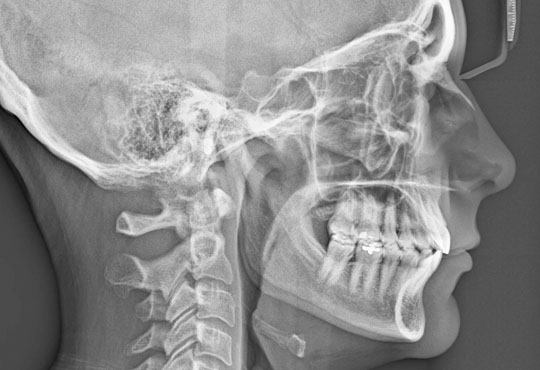

Whole body can be X rayed as and when needed with state of the art high resolution X Ray obtained by Shimadzu Q rad High frequency X Ray machine and Kodak CR System. In addition, Genuine 60 MA portable X Ray unit is available for at Home / bedside X ray.